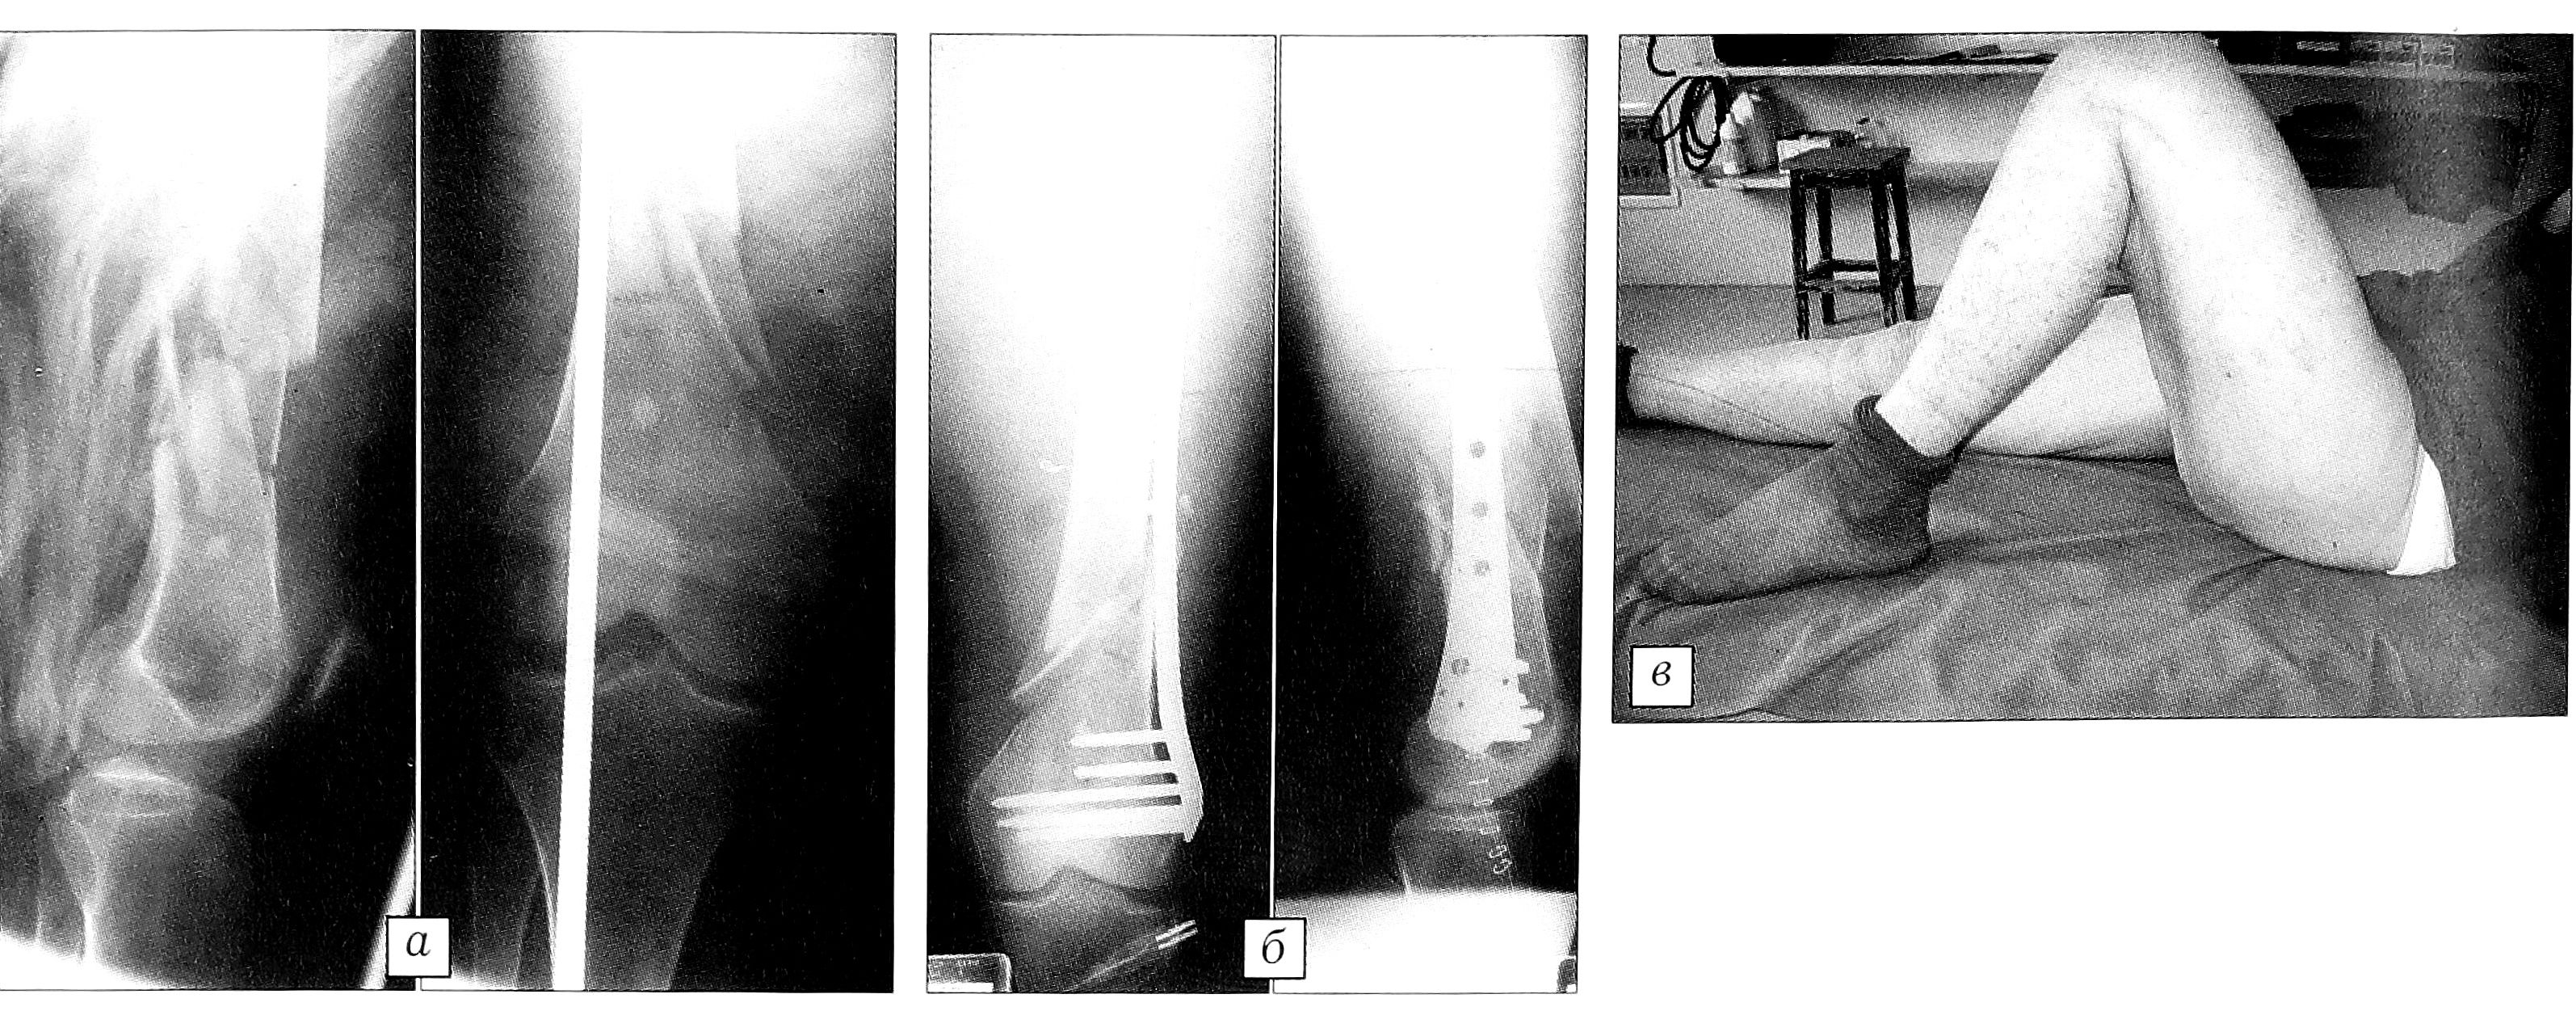

Больная Х.,79 лет. Перелом типа 33А. Травма получена при падении во время спуска по лестнице. Остеосинтез пластиной LISS «9 отверстий». Результат через 1 год: хорошая соосность, укорочение конечности 2 см, обем движений 0-110° (рис. 4).

Рис. 4. Больная X. 79 лет. Перелом 33А. а — рентгенограмы перед операцией, б — после операции; в — обем движений через 1 год после операции.